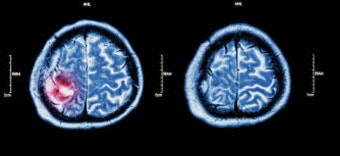

뇌경색은 말 그대로 뇌 조직의 일부가 혈류 차단으로 인해 괴사하는 현상을 말합니다. 이는 뇌혈관이 막히면서 발생하는 것으로, 산소와 영양분을 공급받지 못한 뇌세포가 죽기 시작하는 상태입니다. 대부분 혈전(피떡)이 원인이며, 갑작스럽게 뇌로 가는 피의 흐름이 멈추면서 해당 부위의 뇌세포가 손상되죠.

이런 뇌세포의 손상은 신체의 다양한 기능 장애를 일으킵니다. 예를 들어, 뇌의 좌측이 손상되면 우측 신체에 마비가 오거나, 말이 잘 나오지 않는 언어장애가 발생할 수 있습니다. 반대로 우측 뇌에 손상이 생기면 좌측 신체에 이상이 생길 수도 있죠. 즉, 뇌경색의 위치에 따라 증상의 양상이 달라지는 것입니다.

많은 사람들이 뇌경색과 뇌출혈을 혼동하곤 합니다. 둘 다 뇌졸중의 일종이지만 발생 원리와 증상이 다릅니다. 뇌경색은 ‘혈관이 막혀서’ 생기는 것이고, 뇌출혈은 ‘혈관이 터져서’ 생기는 것입니다. 즉, 뇌경색은 피가 뇌로 가지 못해서 문제가 생기는 것이고, 뇌출혈은 피가 뇌 안에 퍼져서 문제가 생기는 것이죠.